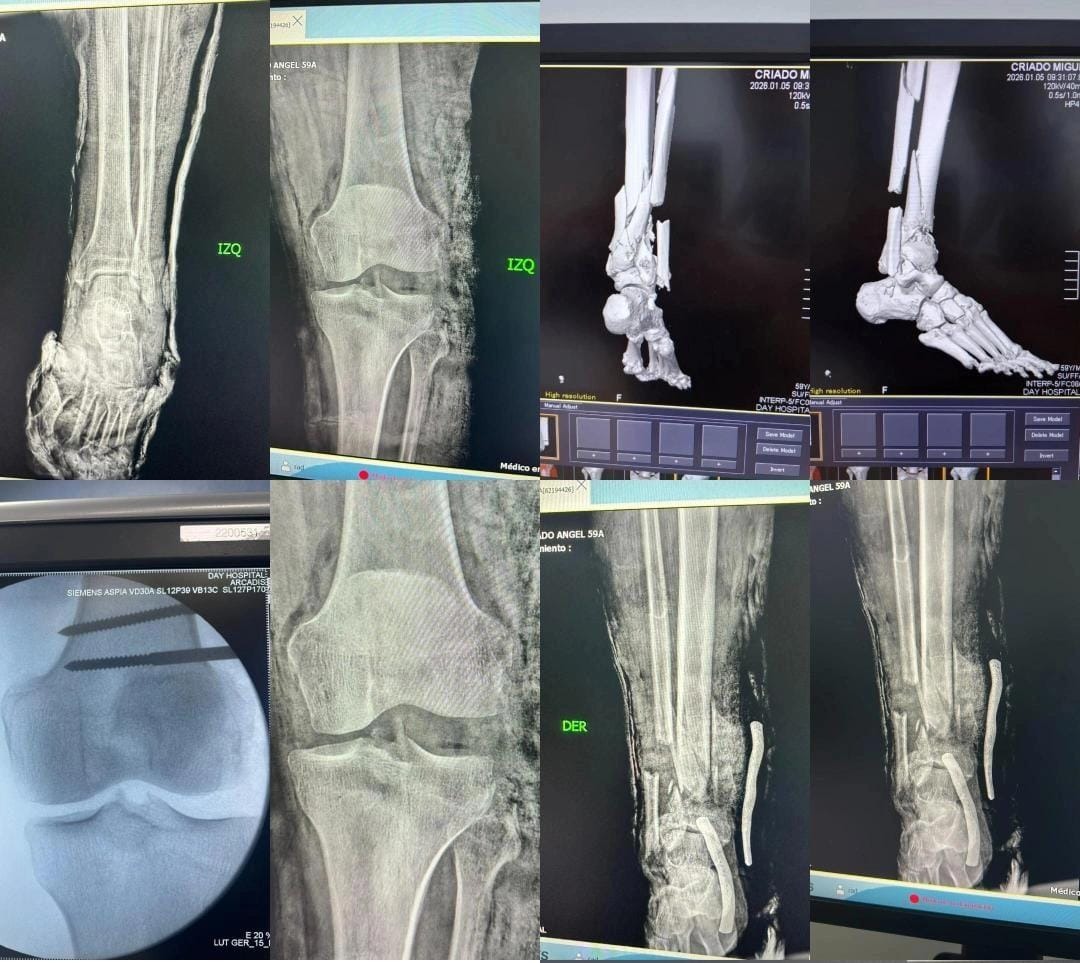

En la mañana del 4 de enero del 2026, me encontraba con mis papás vacacionando en el Estado Anzoátegui. Mi papá se dirigió al balcón a ver el paisaje, cuando la estructura que no estaba soldada de un extremo colapsó, provocando su caída al vacío. En cuestión de segundos nos asomamos y mi papá estaba agonizando del dolor, con el pie derecho completamente roto y separado de la pierna, sangrando a su vez de la pierna izquierda sin parar. El balcón no se encontraba en óptimas condiciones, generando laceraciones en los glúteos y múltiples fracturas en las piernas de mi papá Miguel Angel Criado González.

El diagnóstico fue:

1. Politraumatismo generalizado complicado.

2. Traumatismo postraumático de la rodilla izquierda complicado con exposición tendinosa, muscular y vascular a descartar.

3. Fractura conminuta expuesta de ⅓ distal de tibia y peroné derecho complicado con pérdida ósea y muscular.

4. Herida anfractuosa en cara medial del calcáneo derecho complicado con exposición tendinosa del tendón aquiles.

Actualmente no se han hecho responsables en su totalidad de los costos de la recuperación, los cuales incluyen: Tratamiento por infección (debido a la fractura abierta). Futura reconstrucción de ligamentos y tendones en la rodilla izquierda. Cirugías de reconstrucción en tibia, peroné y talón derecho. Insumos médicos, honorarios de traumatólogos, infectologos y enfermería, etc. Mi padre se encuentra en cama con un tutor, placa y 16 tornillos en la pierna derecha, y un tutor en la rodilla izquierda el cual debería ser retirado a más tardar esta semana. Mi papá estuvo hospitalizado por 6 días en el Day Hospital en Lechería, durante esos días el hotel se hizo responsable de los gastos en su totalidad incluyendo las dos veces que entró al quirófano, hasta que nos regresamos a Caracas el día 9 de enero en ambulancia. Los costos para salvar sus piernas son sumamente elevados y superan nuestras posibilidades.